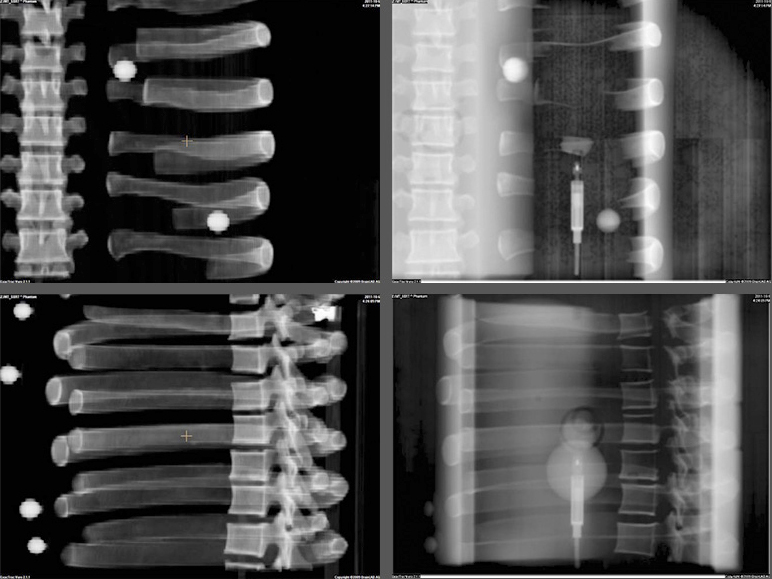

Daily System Checks

The E2E SBRT Phantom contains multiple targets and alignment marks for verifying that imaging, localization, and targeting systems are aligned. This is a critical need for accurate delivery of these high-dose treatments.

Radiochromic Film

The removable split spine allows for film measurements in the sagittal orientation in the inferior half of the spine rod. Film can also be placed in the sagittal slice in the spine and lung inserts.